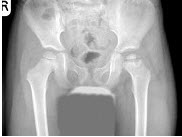

77、单项选择题

男,根据其正常骨盆影像图像,判断其最可能的年龄()

A.6岁左右

B.30岁左右

C.12岁左右

D.18岁左右

E.24岁左右